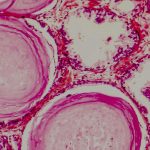

La biopsia de próstata consiste en extraer pequeñas muestras de tejido de la glándula prostática que luego se analizarán para ver su composición. Normalmente, la biopsia de próstata se lleva a cabo para descartar un tumor cuando los niveles de PSA son elevados una vez realizado el control del PSA. Cómo se hace una biopsia […]